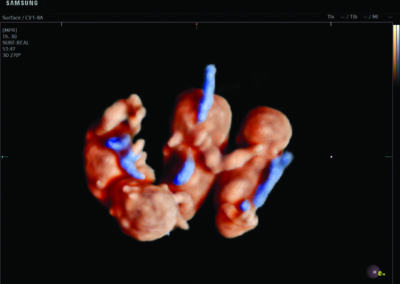

- Multiple births